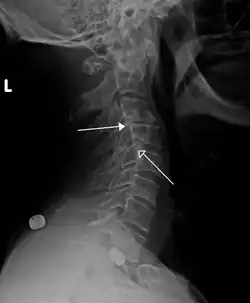

A hangman's fracture is a specific type of spondylolisthesis where the second cervical vertebra (C2) is displaced anteriorly relative to the C3 vertebra due to fractures of the C2 vertebra's pedicles.